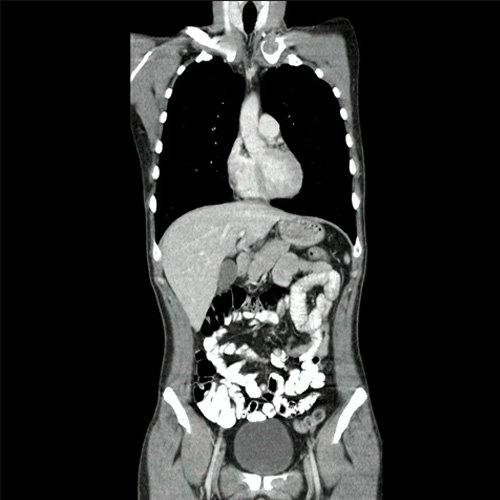

TAC de columna con contraste EV (Corte sagital y corte coronal): Presenta múltiples lesiones líticas óseas, bien circunscritas, que afectan en forma difusa todos los cuerpos vertebrales, sacro, pelvis ósea, esternón, clavícula y escápulas.además se desta